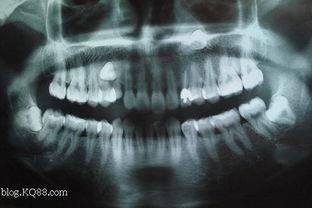

首先,我们要明白,“成人埋伏牙”这个词汇其实是指成年人牙齿生长过程中出现的一种异常情况。简单来说,就是成年后牙齿突然长出来,就像是在牙床里埋伏了一样。这种牙齿问题在网络上引起了广泛关注,很多人通过视频来了解和解决这一问题。

那么,成人埋伏牙究竟是怎么形成的呢?根据口腔医学专家的研究,主要有以下几个原因:

1. 遗传因素:家族中有埋伏牙病史的人,更容易出现这种情况。

2. 牙齿拥挤:牙齿排列不整齐,导致空间不足,新牙无法正常生长。

3. 牙齿缺失:牙齿缺失后,周围的牙齿会向空缺处移动,为新牙的生长腾出空间,但新牙却长在了错误的位置。

4. 口腔不良习惯:如咬笔、咬指甲等,可能导致牙齿生长方向异常。